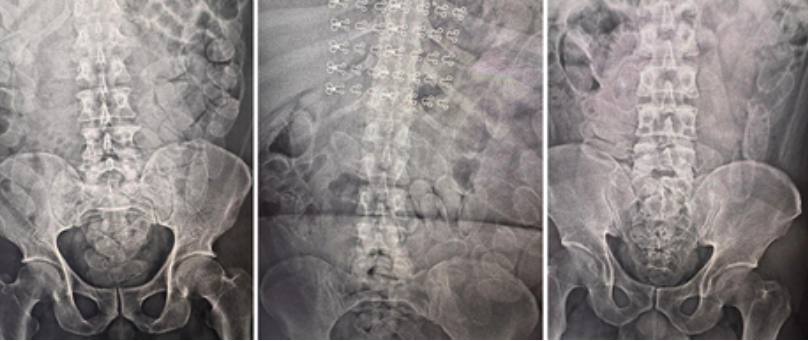

O cão de faro indicou a presença de entorpecentes em uma mochila, o que levou à entrevista dos suspeitos e à identificação de indícios de ingestão de drogas. Os três foram encaminhados à Santa Casa de Corumbá, onde exames confirmaram a presença das cápsulas no organismo.

Após a expulsão das substâncias, os detidos serão entregues à Polícia Federal para continuidade das investigações.